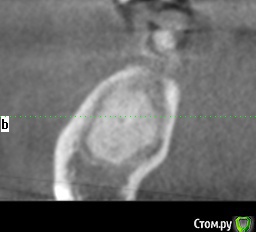

Тимур86 Опубликовано 5 ноября, 2019 Автор Поделиться Опубликовано 5 ноября, 2019 Не стоит бороться со своими желаниями... я бы удалил и гисту провёл, а потом можно и астру думаешь оно инкапсулированное? Мне кажется это типа остеомы, хотел забрать трепаном перед подготовкой ложа и на гистологию Ссылка на комментарий

red_butler Опубликовано 5 ноября, 2019 Поделиться Опубликовано 5 ноября, 2019 думаешь оно инкапсулированное? Мне кажется это типа остеомы, хотел забрать трепаном перед подготовкой ложа и на гистологиюДа, вроде капсула есть 1 Ссылка на комментарий

Тимур86 Опубликовано 5 ноября, 2019 Автор Поделиться Опубликовано 5 ноября, 2019 Ну вот на панораме вроде есть, а на срезах не сказать Ссылка на комментарий

Тимур86 Опубликовано 1 октября, 2020 Автор Поделиться Опубликовано 1 октября, 2020 Есть похожая ситуация! Но тут сложнее :глубже, и в непосредственной близости с нервом... У кого какие мысли? Ссылка на комментарий